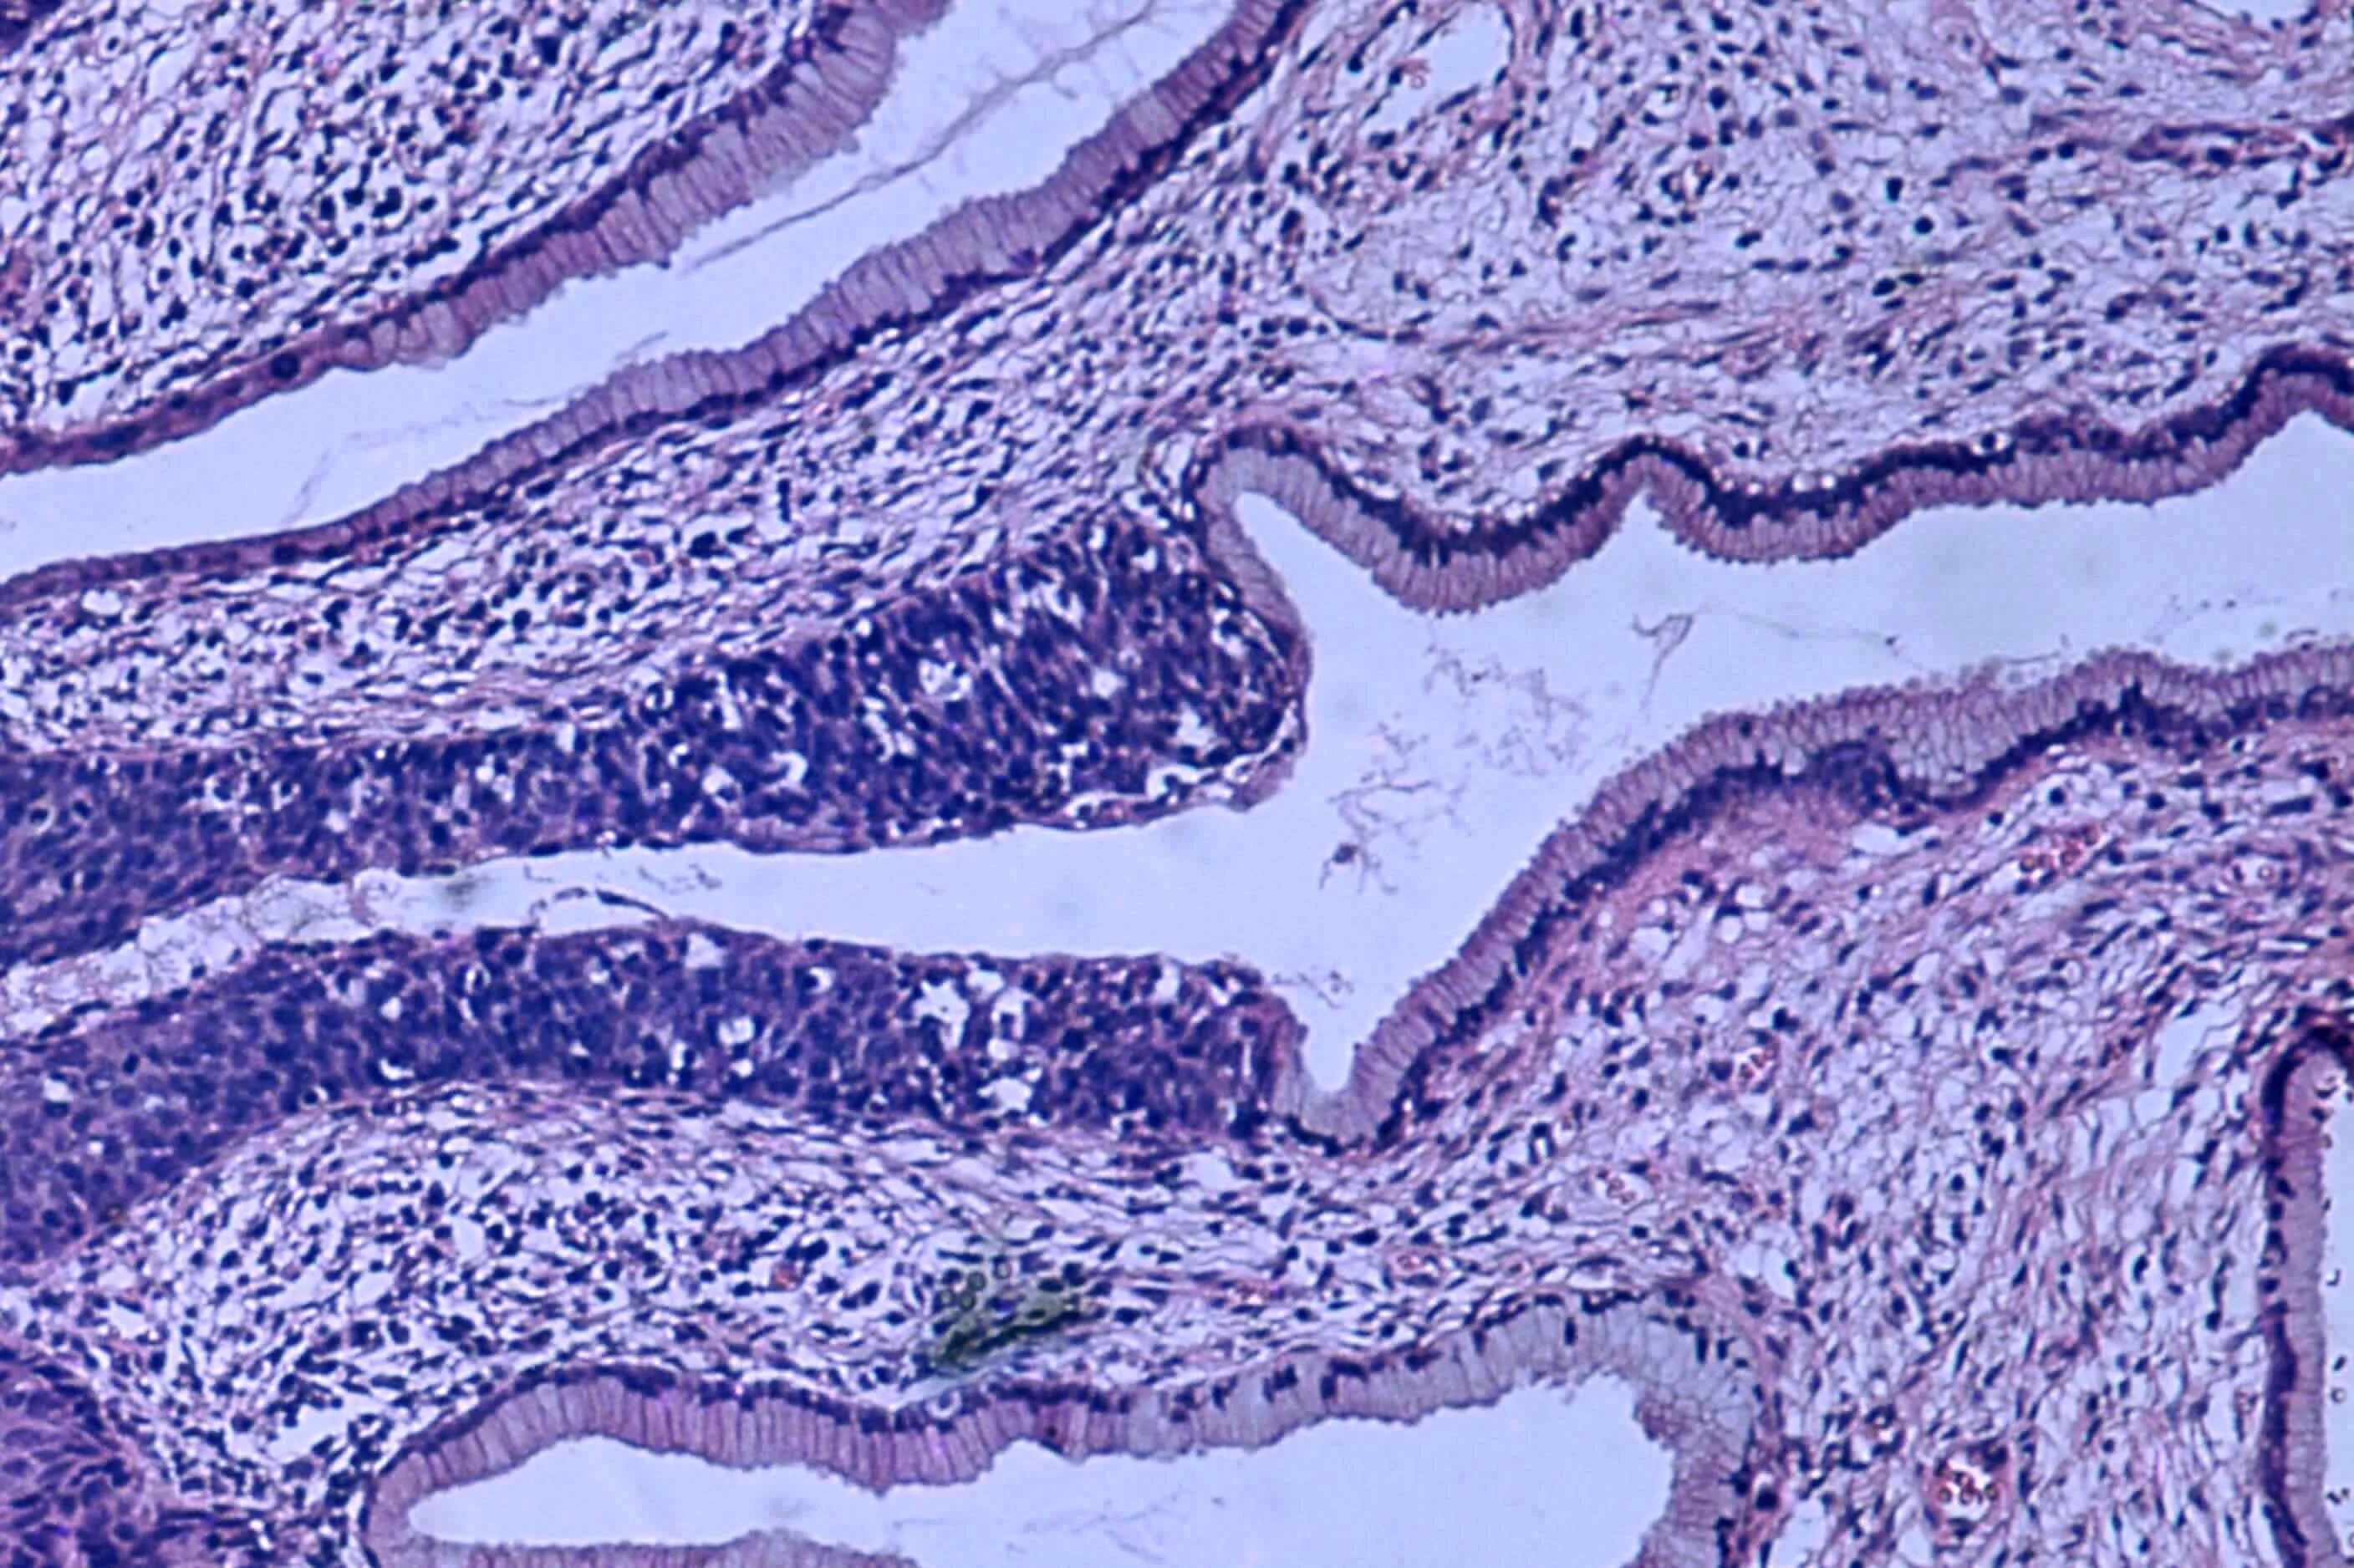

Что показала гистология замершей